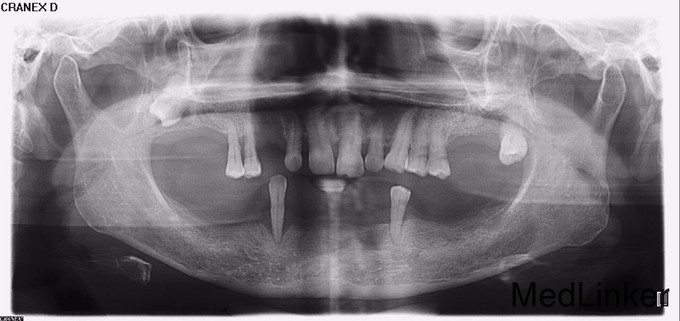

口腔内多颗牙陆续拔除,要求修复

左上后牙多颗牙缺失